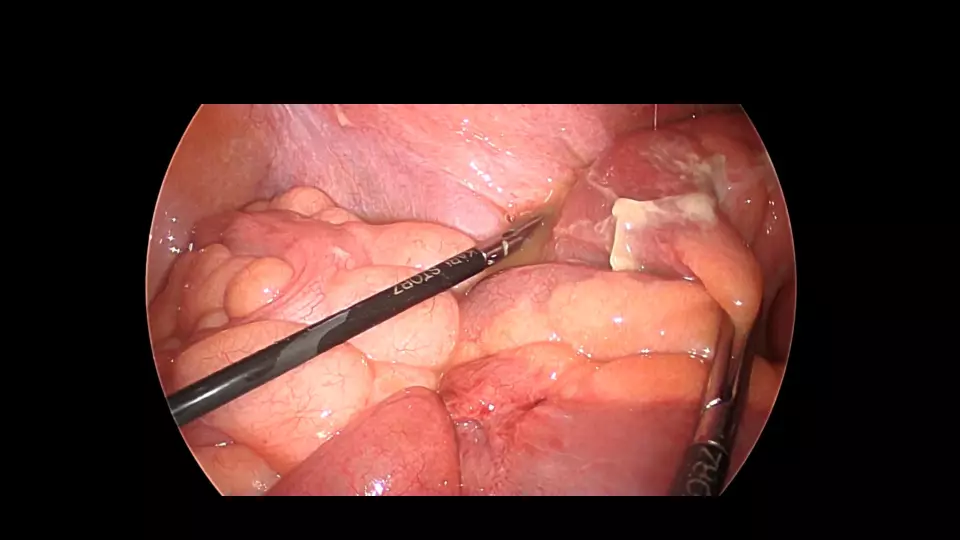

「反跳痛があります」と記載された紹介患者や、研修医からコンサルトにおいて、意外と腹膜炎ではないパターンが散見されます。 若手外科医だからこそ語れる腹膜炎のはなしを聞いてください。 #腹膜炎,#反跳痛の診かた,#コンサルト,

外科医目線の腹膜炎 ~これが腹膜刺激兆候です~